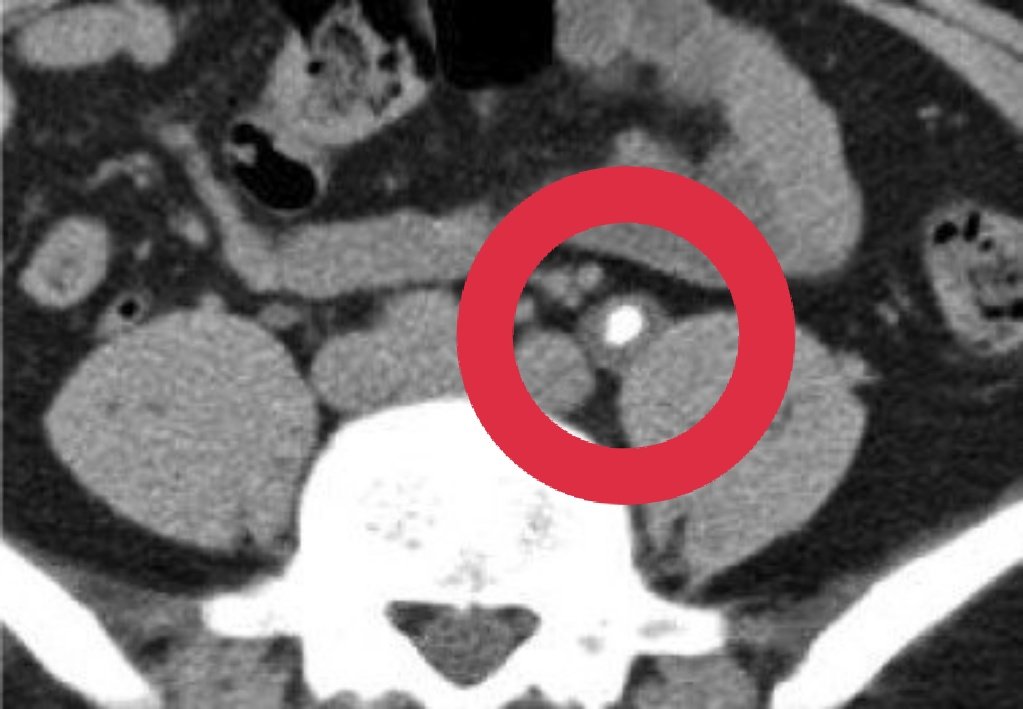

Introducing STONE PASS A community education effort to improve ureteral stone discussions between patient & provider A tool to communicate probability based on outcomes of similar patients (size, location, & #PROMIS pain) It's all about decision making stonepassapp.com